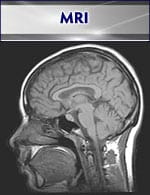

There is a vital need for quantitative assessment of cancer therapy response. Computed tomography (CT) and standard magnetic resonance imaging (MRI) cannot provide information on the biochemical and physiologic properties of cancer tissues. The Hillman IVIF provides novel quantitative imaging techniques that trace biomarkers of molecular events associated with effective cancer therapy. Early imaging of such fundamental molecular pathways corresponding to effective treatment is now playing an increasingly vital role in patient cancer therapy management. Development and use of quantitative imaging for early therapy assessment will become critical to future management by sparing patients weeks or months of toxic and ineffective treatment.